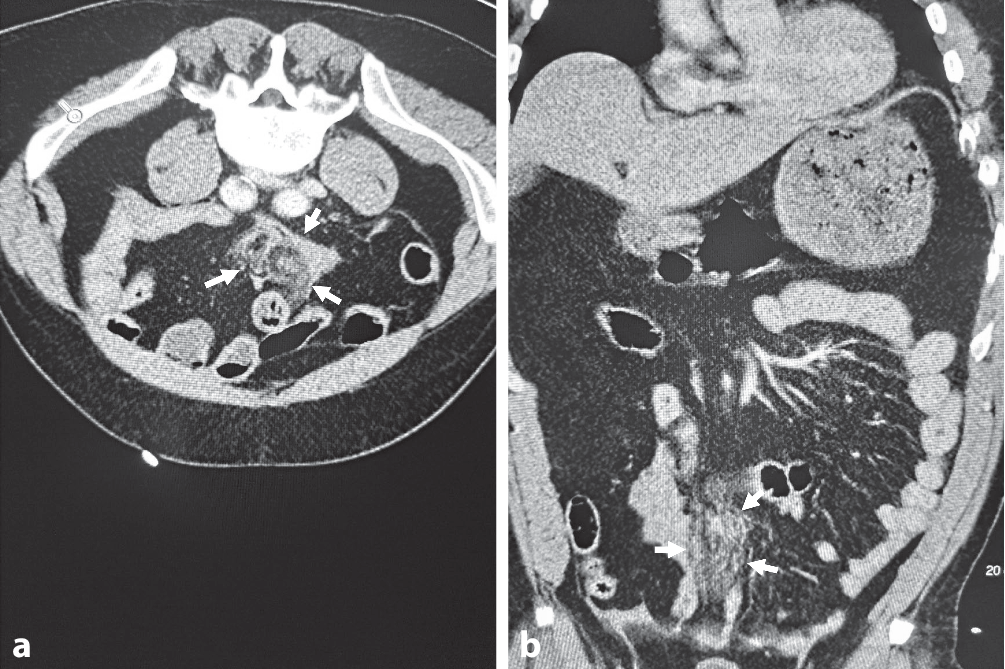

Bei Aufnahme im Schockraum der Zielklinik zeigte sich ein tachykarder (Herzfrequenz 125/min), normotoner (mittlerer arterieller Blutdruck [MAP] 100 mm Hg) und analgosedierter Patient (GCS 11) mit einer Spontanatemfrequenz von 20/min unter 10 l/min Sauerstoff. Der intraabdominelle Flüssigkeitsnachweis um Milz und Blase wurde im Schockraum ultrasonographisch bestätigt und in Rücksprache mit dem Notarzt als größenzunehmend gewertet. Es erfolgte die Gabe von 1 g Tranexamsäure intravenös. Laborchemisch zeigte sich ein Hb 15,6 g/dl bei einem pH 7,269, Lactat 4,4 mmol/l und BE −1,1 mmol/l; als Zeichen des Abdominaltraumas waren die Leberenzyme leicht erhöht, und es zeigte sich ein Kreatinin von 1,62 mg/dl als Zeichen einer eingeschränkten Nierenfunktion. Im Rahmen der konventionellen Gerinnungsdiagnostik imponierten eine International Normalized Ratio (INR) 2,75, PTT 38,4 s, Thrombozyten 204/nl und D‑Dimere 18,7 mg/l. Die computertomographische Ganzkörperschnittbildgebung zeigte als intraabdominelle und aktive Blutungsquellen mehrere Mesoeinrisse (Abb. 1); das weitere Verletzungsmuster bestand aus multiplen Lungenkontusionen, einer Dreietagenfraktur des linken Femurs mit begleitender drittgradig offener Fraktur der Patella, einer geschlossenen Unterschenkelfraktur rechts sowie einer Dissektion der linken A. iliaca communis.

Abb. 1

Computertomographischer (CT) Nachweis der aktiven intraabdominellen Blutung. a CT-Transversalebene und b CT-Fontalebene aus diffusen Mesoeinrissen (Pfeile in a und b)